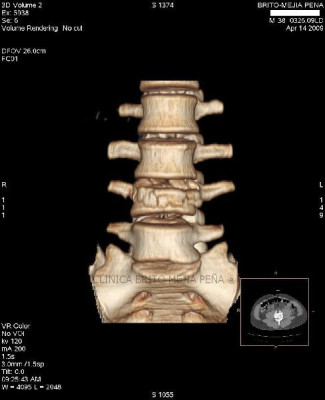

Instrumentalización columna 3D